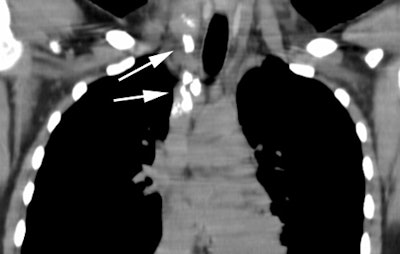

Computed Tomography: CT can detect intrathoracic sites of disease not detected on CXR in up to 20% of patients. The effect on patient management is quite variable (between 10-60% of patients), and is related to the specific protocol for which the patient is being considered. On CT there is usually an asymmetric, anterior mediastinal soft tissue mass which may invade the chest wall. Bulky mediastinal nodal disease can be associated with interstitial edema due to lymphatic/venous obstruction. Although typically homogeneous, larger masses may contain areas of decreased attenuation representing necrosis or cyst formation. Calcification is RARE prior to therapy. A pleural effusion is seen in up to 30% of cases and is usually felt to be related to lymphatic/venous obstruction from the mediastinal mass [ACR Syllabi #40:p.134 suggests effusions are found in only 2% of cases]. Benign pericardial effusions may also be seen in such patients.